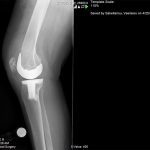

Ο ορθοπεδικός – χειρούργος Βασίλειος Σακελλαρίου στην Αθήνα αντιμετωπίζει επιτυχώς κάθε είδους κακώσεις γόνατος και ισχίου. Παρακάτω παρουσιάζονται πολλές περιπτώσεις κακώσεων που αντιμετωπίστηκαν επιτυχώς από τον χειρούργο – ορθοπεδικό. Δείτε τις αναλυτικά: